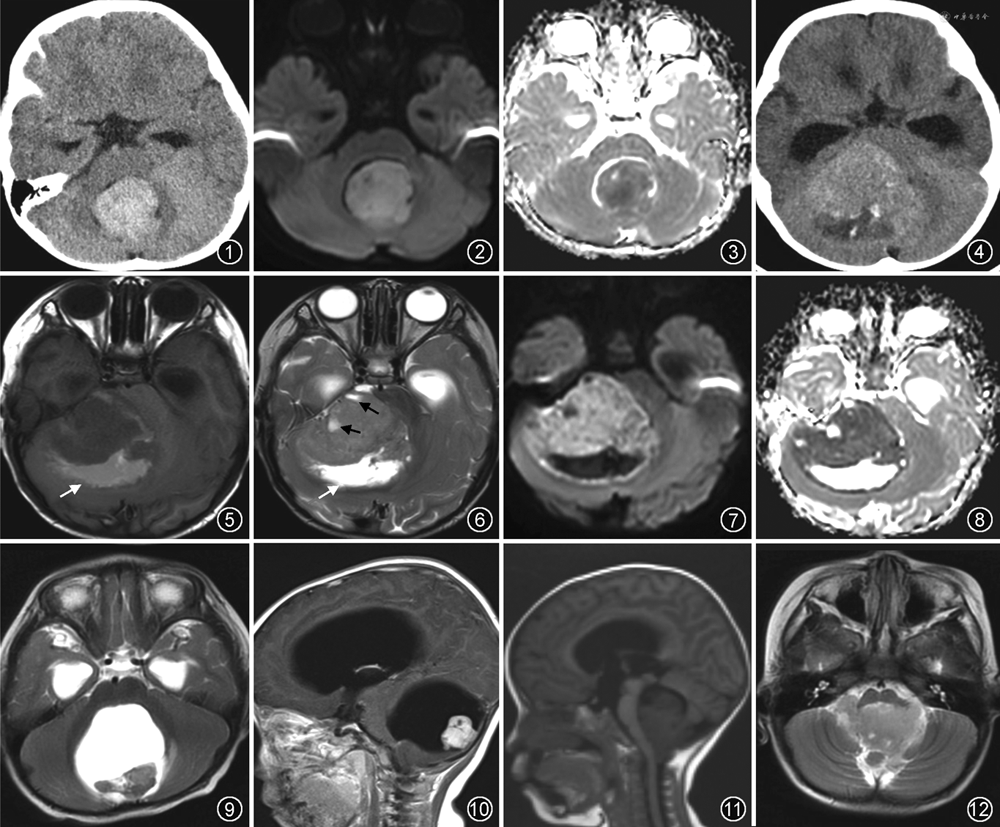

影像诊断要点:CT平扫表现为高密度肿块(图1),肿瘤内钙化及囊变不多见,为较小钙化及囊变。MRI能够更好地显示肿瘤的成分,矢状面图像对于判断肿瘤的部位和起源、明确肿瘤与第四脑室、脑干和小脑的关系非常重要。MRI平扫肿块于T1WI呈等-稍低信号,于T2WI呈稍高-高信号,瘤周水肿不明显。DWI序列肿块呈高信号(图2),ADC图信号减低(图3),表现为明显扩散受限,为其诊断关键点,其原因为肿瘤内细胞排列密集,细胞核与细胞质比率高,基质稀少,水分子扩散受限。MRS表现为N-乙酰天冬氨酸峰明显减低,胆碱峰明显升高。MRI增强表现缺乏特异性,肿瘤实质部分强化程度可为轻度至明显强化,强化方式可为均质或呈不均质斑片状强化。由于髓母细胞瘤可经脑脊液通路传播,导致颅内或椎管内蛛网膜下腔播散,因此,对整个神经轴进行MRI增强检查明确是否出现脑膜或脊膜侵犯非常必要。

影像诊断要点:肿瘤体积通常较大,常见瘤周水肿,肿瘤呈囊实性,囊性部分多呈偏心性分布于肿瘤周边。CT表现为不均匀高密度肿块(图4),可伴有出血、囊变坏死和钙化,钙化并非其特异性表现。MRI显示肿瘤成分更加清晰,肿瘤整体呈混杂信号。MRI平扫实性部分于T1WI呈等信号,T2WI呈等-稍高信号;囊变坏死区于T1WI呈低信号,T2WI呈高信号,多位于肿瘤周边;肿瘤内出血可因出血所处的时期不同表现为不同信号(图5,6)。于DWI实性部分呈高信号(图7),ADC图信号减低(图8),是非典型畸胎样/横纹肌样瘤诊断的必要条件,原因为其属于小圆细胞恶性肿瘤,细胞密集度高,核质比大,水分子明显扩散受限[13]。MRI增强肿瘤呈不均匀强化,“曲带状”强化具有特征性[14]。非典型畸胎样/横纹肌样瘤恶性度高,部分病例发生脑脊液播散,可见柔脑膜强化。

影像诊断要点:肿瘤多为囊实性,瘤周水肿较轻,典型表现为囊性伴壁结节。CT平扫显示肿瘤边界清楚,囊性成分呈低密度,实性成分呈等密度,第四脑室呈受压表现。CT增强实性成分明显强化。MRI平扫肿瘤囊性部分于T1WI呈低信号,T2WI呈高信号,壁结节于T1WI和T2WI均呈等信号(图9),DWI示扩散受限不明显。MRI增强壁结节呈明显强化,囊性部分及囊壁无强化(图10)。少数情况下,当囊壁出现环形强化时说明囊性部分为肿瘤坏死形成。不典型情况下,毛细胞型星形细胞瘤也可表现为完全实性或不规则囊实性,增强后实性成分均可见强化,此时其与髓母细胞瘤或非典型畸胎样/横纹肌样瘤的主要鉴别点在于毛细胞型星形细胞瘤实性部分于DWI无明显扩散受限。

影像诊断要点:CT表现为第四脑室内不均质肿块,多呈等-稍低密度,钙化常见,高达60%可见钙化,多伴有囊变坏死,也可伴有出血。肿瘤形态不规则,生长方式具有特点,可沿第四脑室侧孔向外生长(图11,12)。MRI平扫肿瘤呈混杂信号,实性部分于T1WI呈等-稍低信号,T2WI呈等-稍高信号;囊变坏死区于T1WI呈低信号,T2WI高信号;出血于T1WI呈高信号;肿瘤内钙化或流空血管于T1WI和T2WI均呈低信号。大多数情况下,DWI肿瘤扩散受限不明显,当肿瘤扩散受限明显时,提示其生物学级别增高,具有间变性趋势。增强检查肿瘤呈不均匀强化,实性部分呈轻-中度强化,强化方式不具特征性。